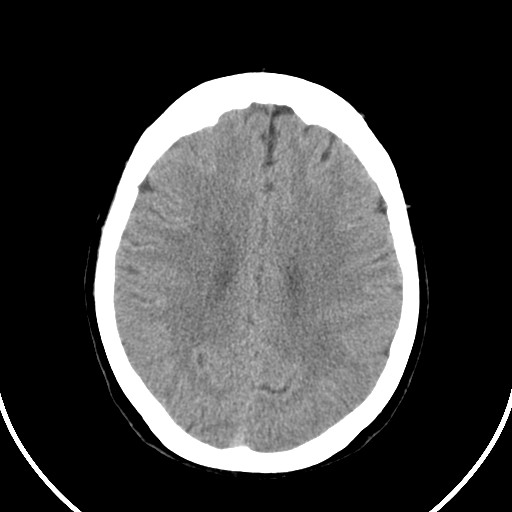

标题: CT21850:女,56岁,右中指淤肿,右手麻痹1天

女,56岁,右中指淤肿,右手麻痹1天

右侧侧脑室旁脑白质腔隙性脑梗死。

右侧基底节多发小梗塞

作者: huangyinshan    时间: 2009-8-25 15:37

右基底结区腔梗

右侧基底节区腔隙性脑梗塞

右侧基底节多发腔梗!

双侧侧脑室额角旁对称性略低密度影,边缘模糊,无占位效应,考虑轻度脑白质稀疏症(病人有高血压吗).,右枕叶低密度影多为伪影,不放心薄扫一下.

考虑脑白质病。

考虑脑白质病